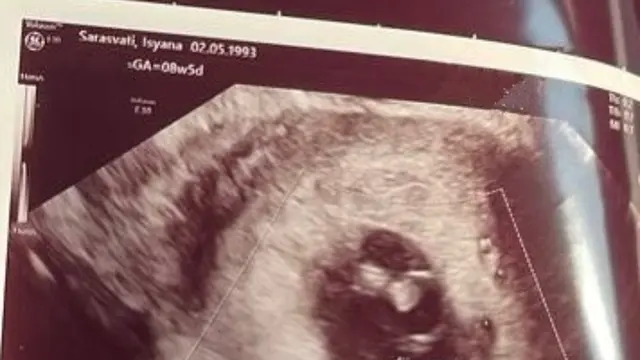

Dalam unggahan itu, Isyana Sarasvati mengunggah dua foto. Foto pertama menampilkan emoji bunga mawar yang layu dan satu lagi terlihat foto USG calon bayi Isyana Sarasvati.

"Malaikat Kecil Kami, datang dengan sayap-sayapnya yang begitu mungil, begitu berharga, memasuki kehidupan kami, ia begitu dekat, momen kerinduan, momen yang kamu dambakan, datangnya kegembiraan, kebenaran yang kami pelajari," tulis Isyana Sarasvati dalam keterangan fotonya.

"Malaikat kami menenangkan hati kami yang penuh ketakutan, keraguan yang ada segera sirna, menjadi jelas, setetes air mata, simbol kehilangan, sampai jumpa lagi, sampai hari kita bertemu - Rayhan Maditra," tambah Isyana Sarasvati.

Meski belum sempat bertemu dengan calon buah hatinya, Isyana begitu sangat mencintainya. Tak hanya itu, dia juga mengucapkan rasa terima kasi pada calon bayi yang sudah mau berjuang sama-sama dalam beberapa waktu terakhir.

"Sampai berjumpa lagi bebinyo. Terima kasih sudah mau berjuang bersama-sama. Sampai jumpa lagi, sampai hari dimana kita bertemu, kami sangat mencintaimu, Bebinyo," tutupnya.